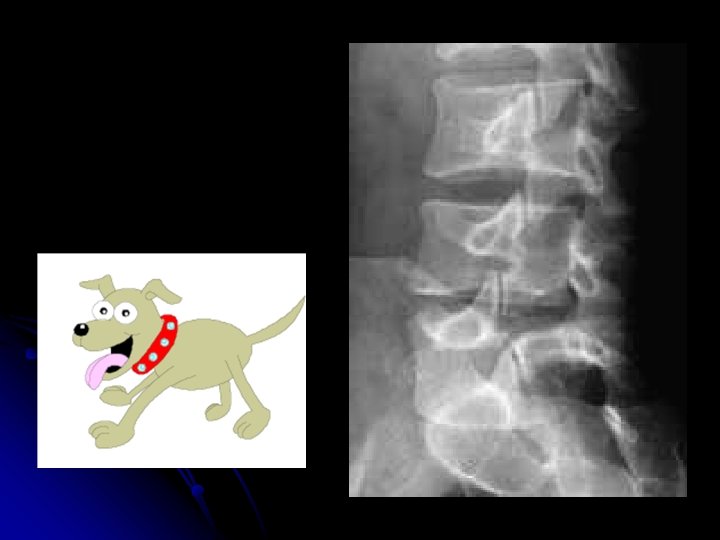

l Autres incidences: l Cliché centré sur L 5 -S 1 l Obliques l Dynamiques

l Rachis dorsal l Le mode radio devra être réalisé avec un champ suffisant pour compter les vertèbres par rapport au sacrum. l Rachis lombaire l La progammation des coupes dépend de l'indication si on n'utilise pas le mode hélicoïdal : l Dans le plan des disques: disques, corps vertébraux, et espace périrachidien ; l Dans le plan des isthmes: l'arc postérieur et en particulier les lyses isthmiques